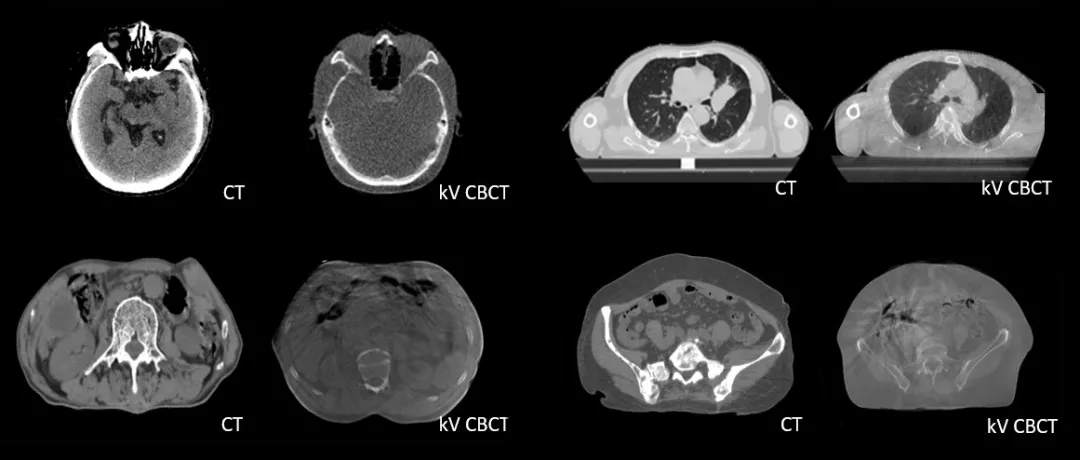

診斷級 CT對比kV-CBCT影像,更好地顯示器官和軟組織的邊界和細節(jié)